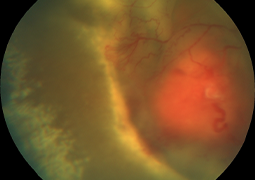

- Outcomes of Chandelier-Assisted Segmental Scleral Buckling Compared to Conventional Scleral Buckling for Primary Rhegmatogenous Retinal Detachment: A comparative retrospective study